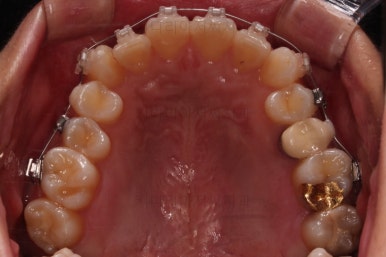

1. 초진

연산동교정치과 초진 시 입안의 모습입니다.

얼핏 앞에서 봤을 때 치열이 나쁘지 않아 보이는데요.

대신 자세히 살펴보면 윗니 양쪽 송곳니가 덧니처럼 볼록 튀어나와 있고요.

아랫니 어금니가 하나 없어서 주위 치아들이 해당 위치로 쓰러진 상태였습니다.

그리고 양쪽의 교합이 톱니바퀴처럼 맞물려 있는 것 같지만 톱니바퀴가 한 칸씩 밀려서 맞물려 있는 부정교합이 있는 상태였습니다.